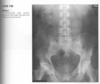

Anteroposterior view of the pelvis

shows diffuse,

uniform, bony sclerosis and a subtrochanteric frac-

ture of the proximal left femur.

A lateral chest ra-

diograph shows the

sandwich appearance of the vertebral bodies caused

by increased sclerosis of the superior and inferior

end plates.

Radiographs of the knees show splaying of the metaphyses and alternating radiolucent bands in the distal

femurs and proximal tibias and fibulas bilaterally. (Erlenmyer flask)

Diagnosis: Osteopetrosis

Defect in osteoclastic resorption.

Precocious (AR Lethal) and Delayed (AD asymptomatic)

Generalized osteosclerosis and diffuse cortical thick-

ening with narrowing of the medullary cavity.